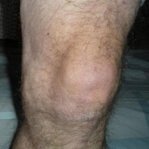

Umflăturile și inflamațiile genunchilor avertizează asupra unor probleme serioase. Fără tratament, acestea pot duce la pierderea completă a mobilității și chiar la necesitatea unei operații. Acționează imediat la primele simptome!